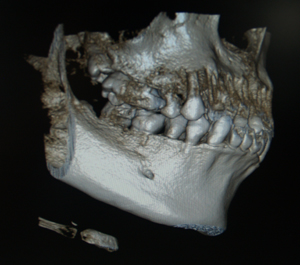

2﹒可快速將拍攝畫面導入影像軟體中,提供多項影像的操作功

......能例如:植牙、矯正.....等。

6﹒同時擁有2D與3D資料管理系統,增加影像分析的準確性。